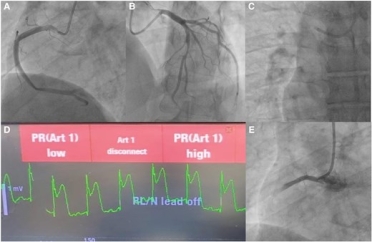

Silent stenosis to sudden shock: the unplanned culprit

What are the next best steps in the management of this patient?

- IV heparin, dual antiplatelet therapy, glycoprotein IIb/IIIa inhibitors, consideration of thrombectomy.

- Vasopressor support, urgent transthoracic echocardiography, preparation for mechanical circulatory support—request cardiothoracic surgeon backup.

- Intracoronary nitroglycerin, serial ECG monitoring, repeat angiographic views, possible PCI.

- Supplemental 100% oxygen, guidewire insertion, catheter aspiration through guiding/microcatheter, intracoronary saline/contrast flushes, intracoronary vasodilators (e.g. adenosine, nitroprusside).